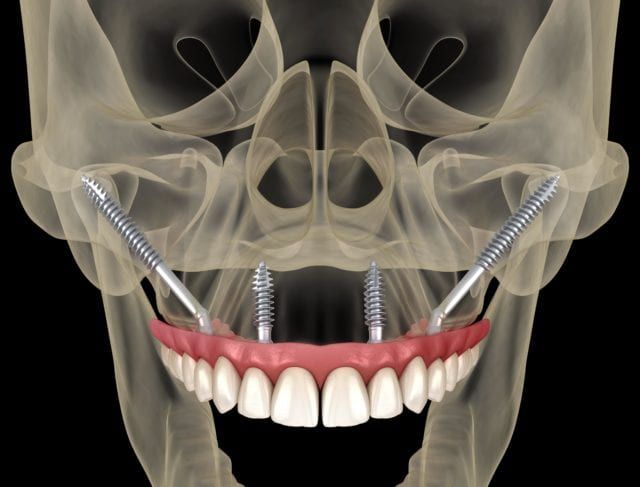

Zygomatic Dental Implants

A reliable dental implant option for patients with severe upper jaw bone loss—no bone grafting required.

Benefits of Zygomatic Implants

- Fixed teeth delivered the same day

- No bone grafting or sinus lift needed

Who Can Place Zygomatic Implants?

This advanced surgical technique requires a high level of skill and training. At FishHawk Oral & Facial Surgery, our team is formally trained and experienced in zygomatic implant placement, ensuring safe and accurate results.

Our team is proud to offer zygomatic implants to individuals who have experienced significant bone loss in the upper jaw and need a dependable alternative to traditional implants. These implants have been used successfully for decades and are backed by long-term clinical success.